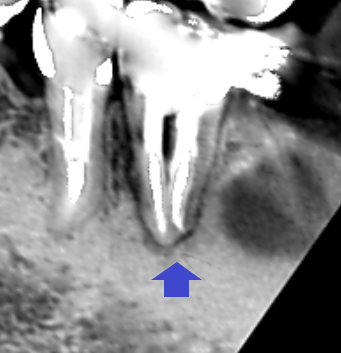

初診時の下顎第一大臼歯の冠状断のCT画像です。

矢印の先に、舌側に根の沿って長い影が認められます。歯根に沿った長い影がみられるときは、歯根破折の可能性があります。